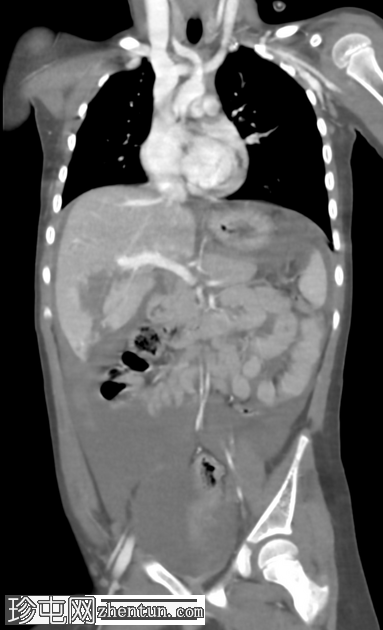

冠状C+门静脉期

AAST IV级肝撕裂伤,伴有大面积不规则肝损伤,累及V段(轴向、冠状、矢状)。

撕裂伤区域内未见活动性造影剂外渗。

可见中等量腹腔积血。

右髂前骨骨折。

无气腹。